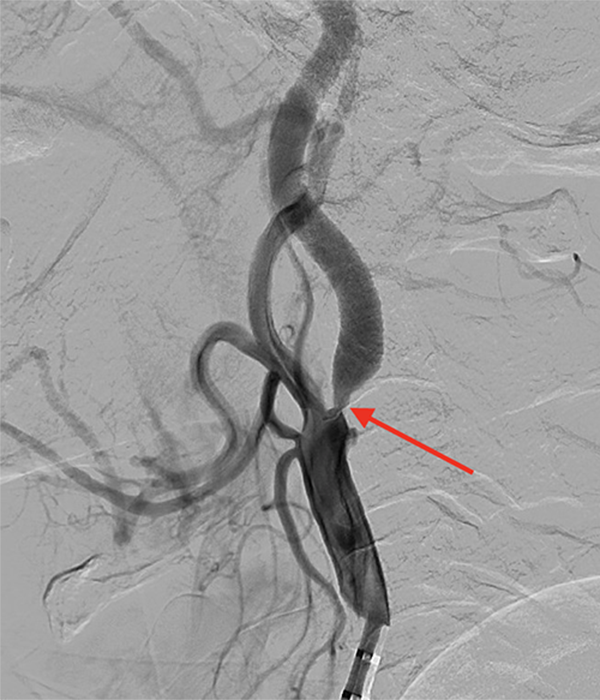

実際の症例